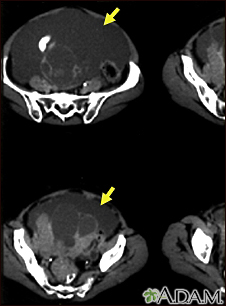

Ascites with ovarian cancer - CT scan